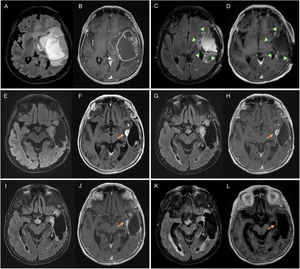

Figure 1.32-year-old man diagnosed with grade 4 IDH-mutant astrocytoma in the left frontal-insular region. Diagnostic MRI with FLAIR (A) and post-contrast T1-weighted (B) sequences. Baseline MRI corresponding to post-radiotherapy MRI, with altered pericavity signal in FLAIR (C), without parietal involvement (D), or contrast enhancement (E). After 20 months of follow-up, a repeat MRI (F–J) showed a new measurable non-enhancing lesion (yellow circle) in the parietal region, corresponding to disease progression. It was decided to perform yet another MRI (K,L), with disease progression confirmed after the increase in the non-enhancing lesion (blue circle) and the appearance of leptomeningeal dissemination (arrow). There is also a pericavity enhancement component (asterisk), but it is not measurable.

IDH: isocitrate dehydrogenase gene; MRI: magnetic resonance imaging.

The measurement is performed on CE tumour (Fig. 2) and the measurement is re-incorporated in T2/FLAIR images of nCE tumour (Fig. 1). In GB it is recommended to measure only the CE tumour (Fig. 2) and in IDHm and other non-GB gliomas without CE tumour, to measure the nCE tumour (Fig. 1). In cases of GB without CE tumour (molecular GB), nCE tumour assessment is possible, until the appearance of measurable CE tumour. In the case of IDHm and other non-GB gliomas with a mixture of CE and nCE tumour, measurement of both components is possible.

New lesionsTo confirm a change in response category due to the appearance of new lesions, they would have to be ML and automatically mean DP (Figs. 1 and 4). Only if they occur in the period when conMRI is required (less than 12 weeks after the end of RT), new contrast-enhancing or non-enhancing lesions do not automatically mean DP, and we should expect to detect growth of such lesions in the conMRI and that the increase in size corresponds to DP thresholds (Fig. 5).

The appearance of leptomeningeal dissemination visible on MRI, although not measurable, also suggests DP (Fig. 1).

As PsP is directly related to contrast enhancement, when nCE progression is suspected in non-GB lesions, a conMRI would not be necessary (Fig. 1).